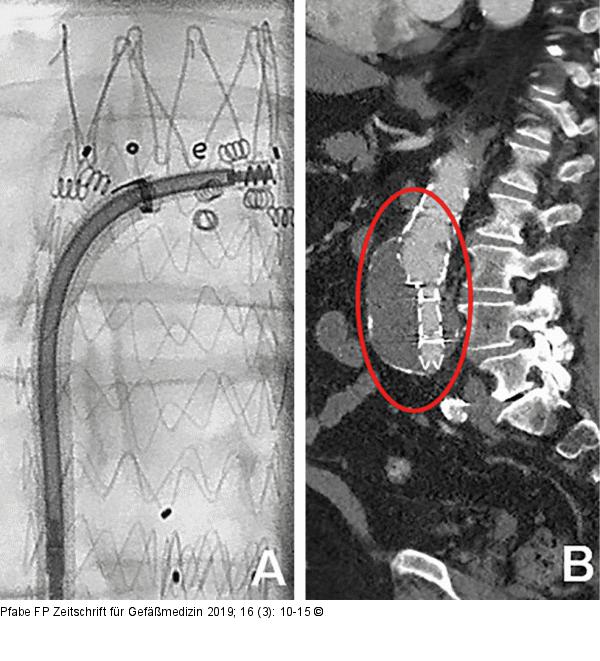

Abbildung 3: Endoleak Typ I Rezidiveingriff bei Endoleak Typ Ia. (A): Angiographische Darstellung (LAO 7°, CRAN 3°) der Fixierung und Abdichtung der Prothese durch Implantation von 9 EndoAnchor; (B): CT-Angiographie (sagittale Rekonstruktion) nach Sekundärprozedur, kein Nachweis eines Endoleaks Typ Ia. |

Rezidiveingriff bei Endoleak Typ Ia. (A): Angiographische Darstellung (LAO 7°, CRAN 3°) der Fixierung und Abdichtung der Prothese durch Implantation von 9 EndoAnchor; (B): CT-Angiographie (sagittale Rekonstruktion) nach Sekundärprozedur, kein Nachweis eines Endoleaks Typ Ia. |